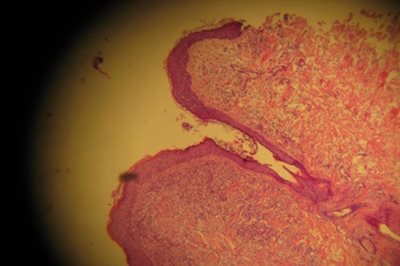

Qu’elles soient directes, guidées échographiquement, grâce à l’endoscopie, par trocart, les biopsies sont des prélèvements de tissus qui sont envoyés à un laboratoire spécialisé en anatomopathologie vétérinaire pour être analysés.

Dans le cadre de la chirurgie carcinologique, le laboratoire permet, pour certaines interventions, une cytologie des marges en direct pour évaluer l’envahissement de celles-ci.